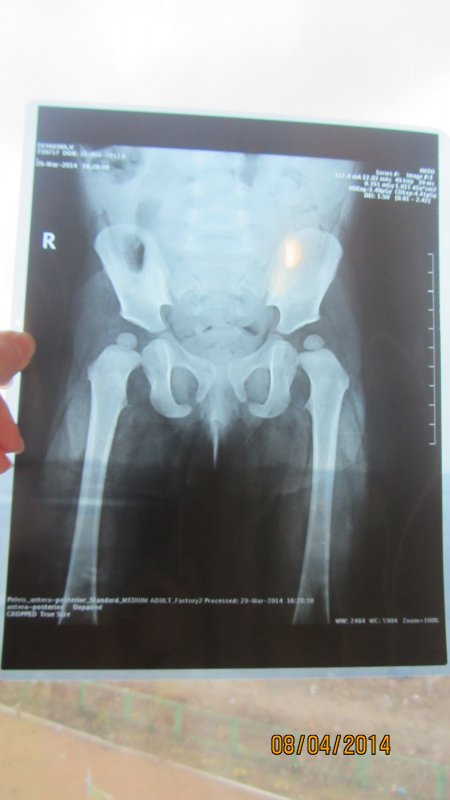

Константин Сергеевич, доброе время суток!!! Очень нужна Ваша консультация!!! Мы просто в отчаянии. Помогите, пожалуйста! Нашей дочки сейчас 1 год и 5 месяцев. В 3 месяца сделали узи т/б суставов- заключение оба сустава-тип Iа. В 6 месяцев пошли на прием к ортопеду: ограничений отведения нет; кожные ягод. и подкол. складки симметр.; длина ног Д=S; ось нижних конечностей правильная, тенденция к вальгусной деформ. стоп.; объем движений в Ш.О.П. полный DS: плосковальгусные стопы. Назначили ЛФК, орторежим, ортообувь с фикс. ГСС. явка в 1 год Мы пришли в 9 месяцев. Нам написали все тоже самое, только добавили мяч и коврик. Явка через пол года. У нас же с 6 месяцев в т/б суставах часто был слышен хруст (щелчек), когда я меняла памперс , однако массажист говорил, что ничего не хрустит (массаж мы делали 5 раз)(массажист у нас врач-хирург) На этом дело и было бы закончено НО!! Хруст все же продолжался. Мы сделали узи т/б суставов в 1,1месяц в НИИТО заключение: признаки задержки темпов оссификации ядер, оба сустава- тип 1а. Затем отправились на консультацию к ортопеду в НИИТО. назначили: ЛФК, массаж, орто обувь, электрофорез, парафин, плавание, Д3 в возростной дозировке, ходьба по коврику, мультитабс малыш кальций 1/4 т. творог, мясо и ренгенография т/б в прямой проекции через 3 месяца. Сходили еще к одному ортопеду, нам сказали ренген делать не обязательно у вас нет дисплазии. Однако мы всеже сделали ренген в НИИТО в 1,5 месяцев и результат по нему такой:- ядра окостенения головок бедренных костей расположены в проекции ацетабулярной впадины, симметричны, децентрированы; - ацетабулярный угол D=28 S=25; -проекционный ШДУ D=156 S=143; - угол наклона плоскости входа во впадину D=37 S=39; - угол Виберга D= 7 S=11; - линии Шентона изломана слева, линии Кальве не нарушены; - симптом Омбреданна отрицательный с обеих сторон. Заключение: Двусторонняя дисплазия тазобедренных сочленений. Помогите, пожалуйста! Что нам делать? Как к Вам можно попасть на прием?? Очень хочется услышать Ваше мнение!

Здравствуйте. Да, дисплазия есть. По тактике лечения - ответил в ЛС. |

нет, рентгенограмма удовлетворительного качества, ошибки нет. Неправильная укладка всегда заметна на снимках. Да, ребенок уложен неидеально, но качество снимка не сильно пострадало, для постановки диагноза достаточно.

Шину носить в течение 6 мес, снимать можно на купание, массаж (хотя, строго говоря, массажу она не мешает), физиопроцедуры. Остальное время она должна надета. Шина центрирует головки бедренных костей в суставных впадинах, при ее ношении происходит правильное формирование тазобедренного сустава, при этом шина не ограничивает движений в коленных суставах и совсем немного-в тазобедренных. Ношение шины - только на голенях, на нижних их третях (не на бедрах!). |